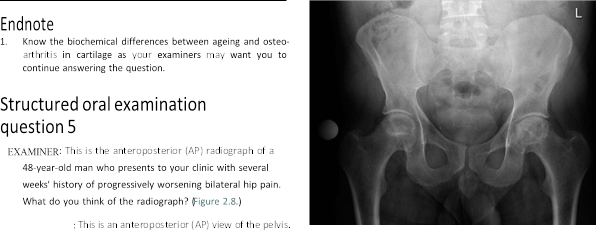

EXAMINER : These are the radiographs of a 78-year-old lady who has been referred to the orthopaedic clinic by her GP because of increasing pain in her right hip. Would you care to comment on the radiographs? (Figure 2.7.) CANDIDATE : This is an AP radiograph, demonstrating lower lumbar vertebrae, both hips and proximal femur. The most obvious features in the right hip are loss of joint space, osteophytes, sclerosis and bone cysts. The radiographic features are highly suggestive of osteoarthritis (OA) of the hip. EXAMINER : How is osteoarthritis classified? CANDIDATE : OA is classified into primary OA when obvious cause can be identified and secondary OA caused by such conditions as avascular necrosis, DDH, post traumatic, Paget’s disease, slipped capital femoral epiphysis, protrusio acetabuli, Perthes’ disease. EXAMINER : What are the percentages of each type of OA? CANDIDATE : Various studies have suggested that almost 90% of cases of OA are secondary. EXAMINER : How are you going to manage this patient? CANDIDATE : I would take a full history and examination from the patient, specifically I would want to know the location of pain, exclude referred pain from the spine. Hip pain is

Figure 2.7 Anteroposterior (AP) radiograph demonstrating severe osteoarthritis of the left hip.